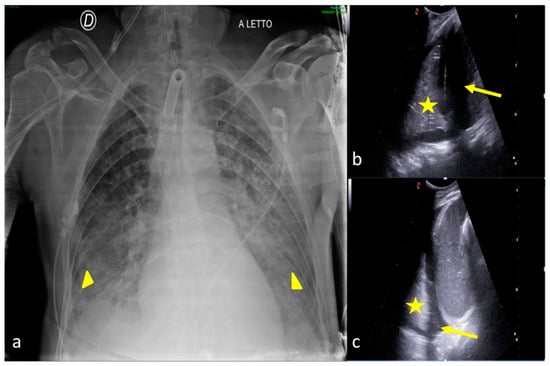

2.3. Pleural Effusion